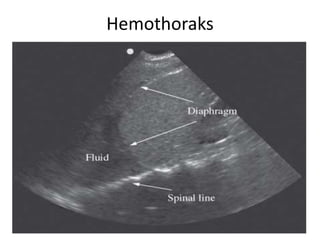

– Hemotoraks

• Regio anechoic diatas dari diafragma

Hemothoraks

• Temuan Abnormal :

– Hemothoraks

• Regio anechoic diantara pleural line dan struktur lain,

jika terdapat bekuan atau materi lain tampak sebagai

bayangan heterogen